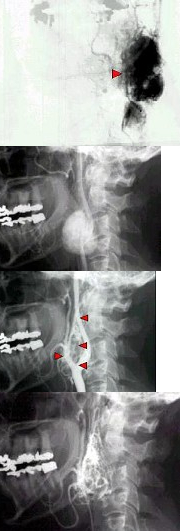

- 单项选择题 女,50岁,颈部无痛性肿块,逐渐增大,听诊可闻及杂音,DSA检查如图所示,最可能诊断( )

A、颈动脉体瘤

- A

- 颈动脉体瘤